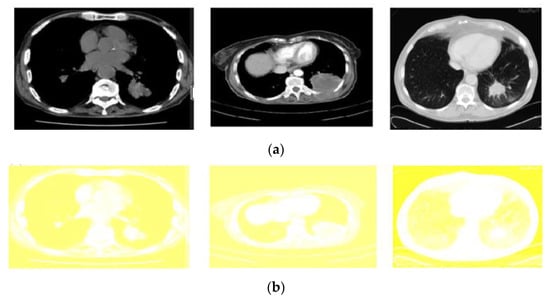

The contrast adjustment of the image was made by histogram equalisation. As a result of such adjustment, a high level of contrast may occur in a particular region. In order to overcome that, the Modified Color Histogram Equalisation was employed in this research. That includes limiting the amplitude of pixel intensities [31]. The transformation function slope and the Cumulative Distribution Function (CDF) are proportionate in this proposed system. The histogram was clipped, and the amplification was limited before computing the CDF. As a result, the CDF and transformation function slopes were reduced. The clip limit [32] is the value at which the histogram is clipped and consequently depends on the size of the neighboring region. Figure 5 shows the applied color-based histogram on the input image (pre-processed).

Figure 5.

Output of the pre-processed images: (a) The original input images (b) corresponding results of modified color-based histogram equalization.